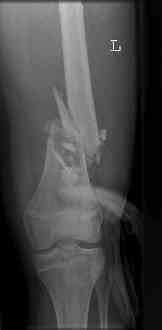

16 yr old boy, high energy motorcycle trauma trauma in July 2005 with:

- hip dislocation + acetabular fracture L

- distal femoral fracture L

July 05

july 05: LISS femur, LCP plate tibia, double recon. plate post. acetabulum